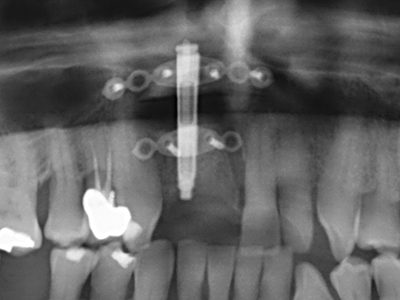

Sollen chirurgische Eingriffe mit unmittelbarer Knochenbeziehung an empfindlichen Strukturen wie Blutgefäßen oder Nerven erfolgen, so bergen rotierende Instrumente ein erhebliches Potential an iatrogener Schädigung. Gerade bei Nervdarstellungen nach iatrogener Schädigung, oder aber im Zuge einer Nervlateralisation für resektive und rekonstruktive Eingriffe oder Implantatinsertionen können piezoelektronische Geräte hilfreich sein Knochendeckel zu präparieren und nervnahe Hartgewebsanteile zu entfernen (Abb. 17-20). Ein leichter Kontakt des Nervstrangs zur Piezospitze bleibt dabei in der Regel folgenlos – allerdings kann eine unvorsichtige Vorgehensweise mit sägeartigen Bewegungen bzw. Ansätzen bei noch vorhandener knöcherner Unterlage durchaus temporäre oder aber auch permanente Nervschädigungen verursachen. Das Risiko einer solchen Schädigung wird jedoch als wesentliche geringer eingeschätzt als unter Anwendung von Säge- oder Fräsinstrumenten (Pereira, Gealh et al. 2014).

Wie sich in der Vergangenheit gezeigt hat stellt prinzipiell jeder knochenchirurgische Eingriff eine mögliche Indikation für die Piezochirurgie dar. So lässt sich die Präparation des mobilen Segmentes bei der Distraktionsosteogenese (Abb. 23-25) und der Sandwichosteotomie mit speziellen Ansätzen bewerkstelligen, ohne die für den Erfolg beider Techniken essenzielle Blutversorgung des krestalen Anteils zu gefährden (Gonzalez-Garcia, Diniz-Freitas et al. 2008).

Für die Entnahme von Implantaten ist die Präparation eines vestibulären Knochendeckels möglich, der nach Entfernung der Implantatschraube refixiert wird und auf diesem Wege die Kontur des Alveolarfortsatzes erhält.